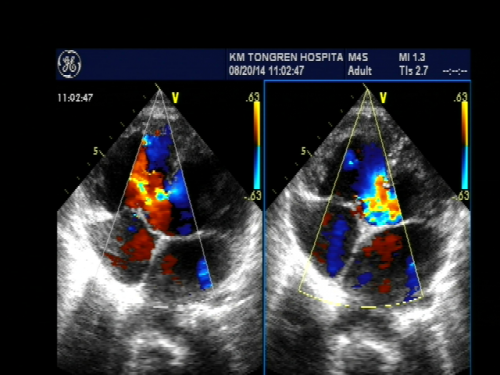

心脏超声是用超声波显示心脏、血管结构的一种检查方法,它分为M型超声、B型二维超声,三维立体超声。心脏超声由声波来探测血流状态和速度,还有彩色心脏超声由彩色血流的方向、压差表现不同的色彩变化,而知道病灶或异常构造的所在。此方法安全,没有放 射性,诊断准确率高,对病人没有痛苦和损伤,价格相对便宜,检查结果迅速及时,可反复多次检查,对很多心脏病的诊断有帮助。

房间隔缺损

室间隔缺损